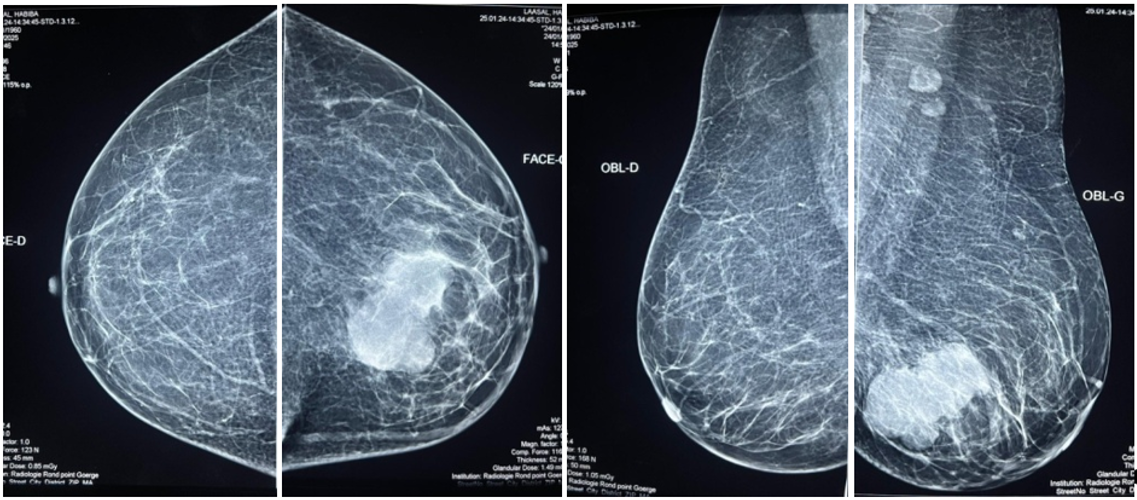

Initial echo-mammography: Suspicious lesion measuring 47x32 mm at the junction of the lower quadrants of the left breast + Left axillary lymphadenopathy, some of which have a thickened cortex, the largest measuring 11x7 mm: Examination classified as ACR5 on the left (Figure 1).

Figure 1: Initial mammo showing a lesion at the junction of the lower quadrants